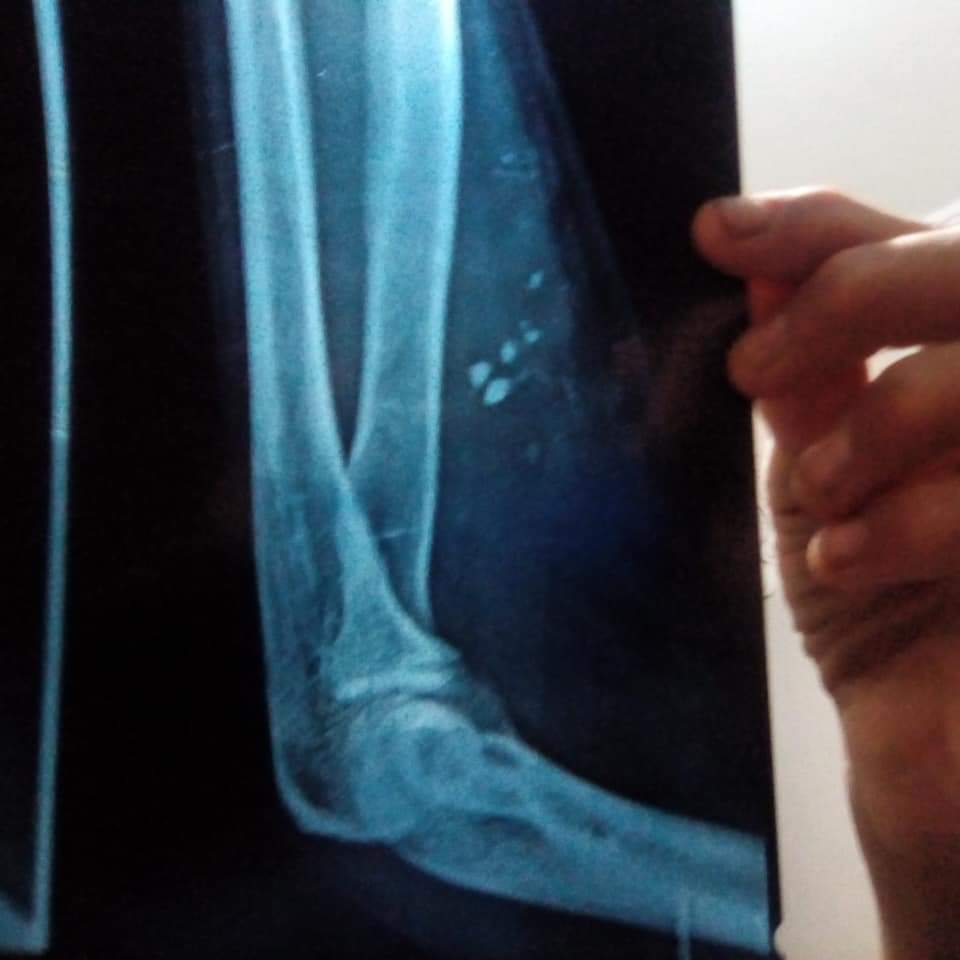

اتجه إلى محافظة القاهرة؛ لإجراء بعض الفحوصات الطبية؛ نظرًا لأنه يشعر بألم شديد وتم عمل أشعة ليتبين أن الجرح بداخله زجاج ولا بد من عمل جراحة عاجلة لتنظيف الجرح وإعادته مرة أخرى.

أشار حسن عبده الصعيدي إلى أن الزجاج ظل داخل ذراعه ما يقرب من 40 يومًا حتى إخراجه بعد عمل جراحة في أحد المستشفيات بمحافظة القاهرة، مطالبًا المسؤولين بمحافظة شمال سيناء بمحاسبة الدكتور المعالج بمستشفى العريش الذي لم يراعِ الله في عمله، وأغلق الجرح دون تنظيفه؛ ما تسبب في ألم جسدي على مدار 40 يومًا.